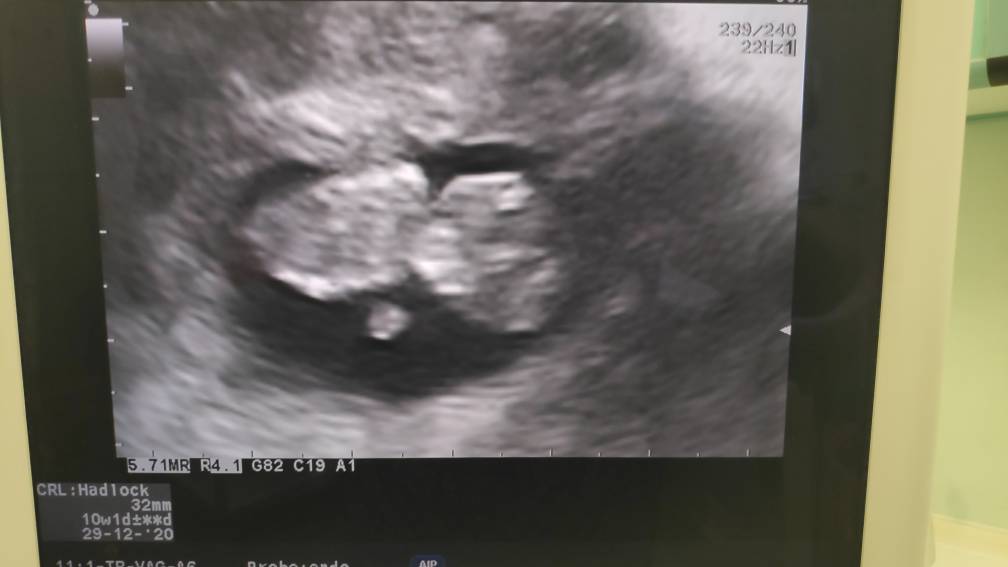

Dziewczyny! Jestem po ❤ a więc tak. Wszystko dobrze, przytyłam niecały kilogram, bąbello ma 7.5cm i nadrobił więc dzisiaj wedlug usg 13+4 i data porodu na 5.12. :)

Ogolnie wiercil sie caly czas i tak kopal nóżkami i rączkami :D odwrócony jest do dołu więc patrzy sobie w stronę moich nóg 😂 ogólnie mowie on... Boooooo na 70% chłopak. :D według mojej doktorki.. Zobaczymy czy potwierdzi sie na prenatalnych pojutrze :D

Oto trzy zdjęcia :D na jednym rączka, na drugim siurek 😂 a na trzecim ON ❤❤

Zobacz załącznik 1128155

Zobacz załącznik 1128156

Zobacz załącznik 1128157